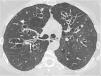

La patología de las vías respiratorias de medio calibre (bronquios segmentarios y subsegmentarios) es común y se presenta con síntomas respiratorios poco específicos, como tos, infecciones de repetición y en ocasiones hemoptisis. La dilatación permanente del árbol bronquial se conoce como «bronquiectasia» y representa un reto diagnóstico. El análisis de la distribución regional de las bronquiectasias en los diferentes lóbulos pulmonares es la guía diagnóstica más útil. El objetivo de este trabajo es describir los hallazgos de imagen de las bronquiectasias y sus diferentes tipos, revisar las situaciones más comunes y proponer un algoritmo diagnóstico basado en su distribución anatómica. Las bronquiectasias son un hallazgo frecuente, resultado de un amplio espectro de enfermedades. Los estudios de imagen desempeñan un papel esencial en su detección, clasificación y orientación diagnóstica hacia la patología subyacente

Diseases that involve the medium caliber airways (segmental and subsegmental bronchi) are common and present clinically with nonspecific respiratory symptoms such as cough, recurrent respiratory infections and occasionally, hemoptysis. The abnormal and irreversible dilation of bronchi is known as “bronchiectasis”. The diagnosis can be challenging and the analysis of the regional distribution of the bronchiectasis is the most useful diagnostic guide. The objective of this manuscript is to describe the main imaging findings of bronchiectasis and their classification, review the diseases that most commonly present with this abnormality, and provide an approach to the diagnosis based on their imaging appearance and anatomic distribution. Bronchiectasis is a frequent finding that may result from a broad range of disorders. Imaging plays a paramount role in diagnosis, both in the detection and classification, and in the diagnosis of the underlying pathology.